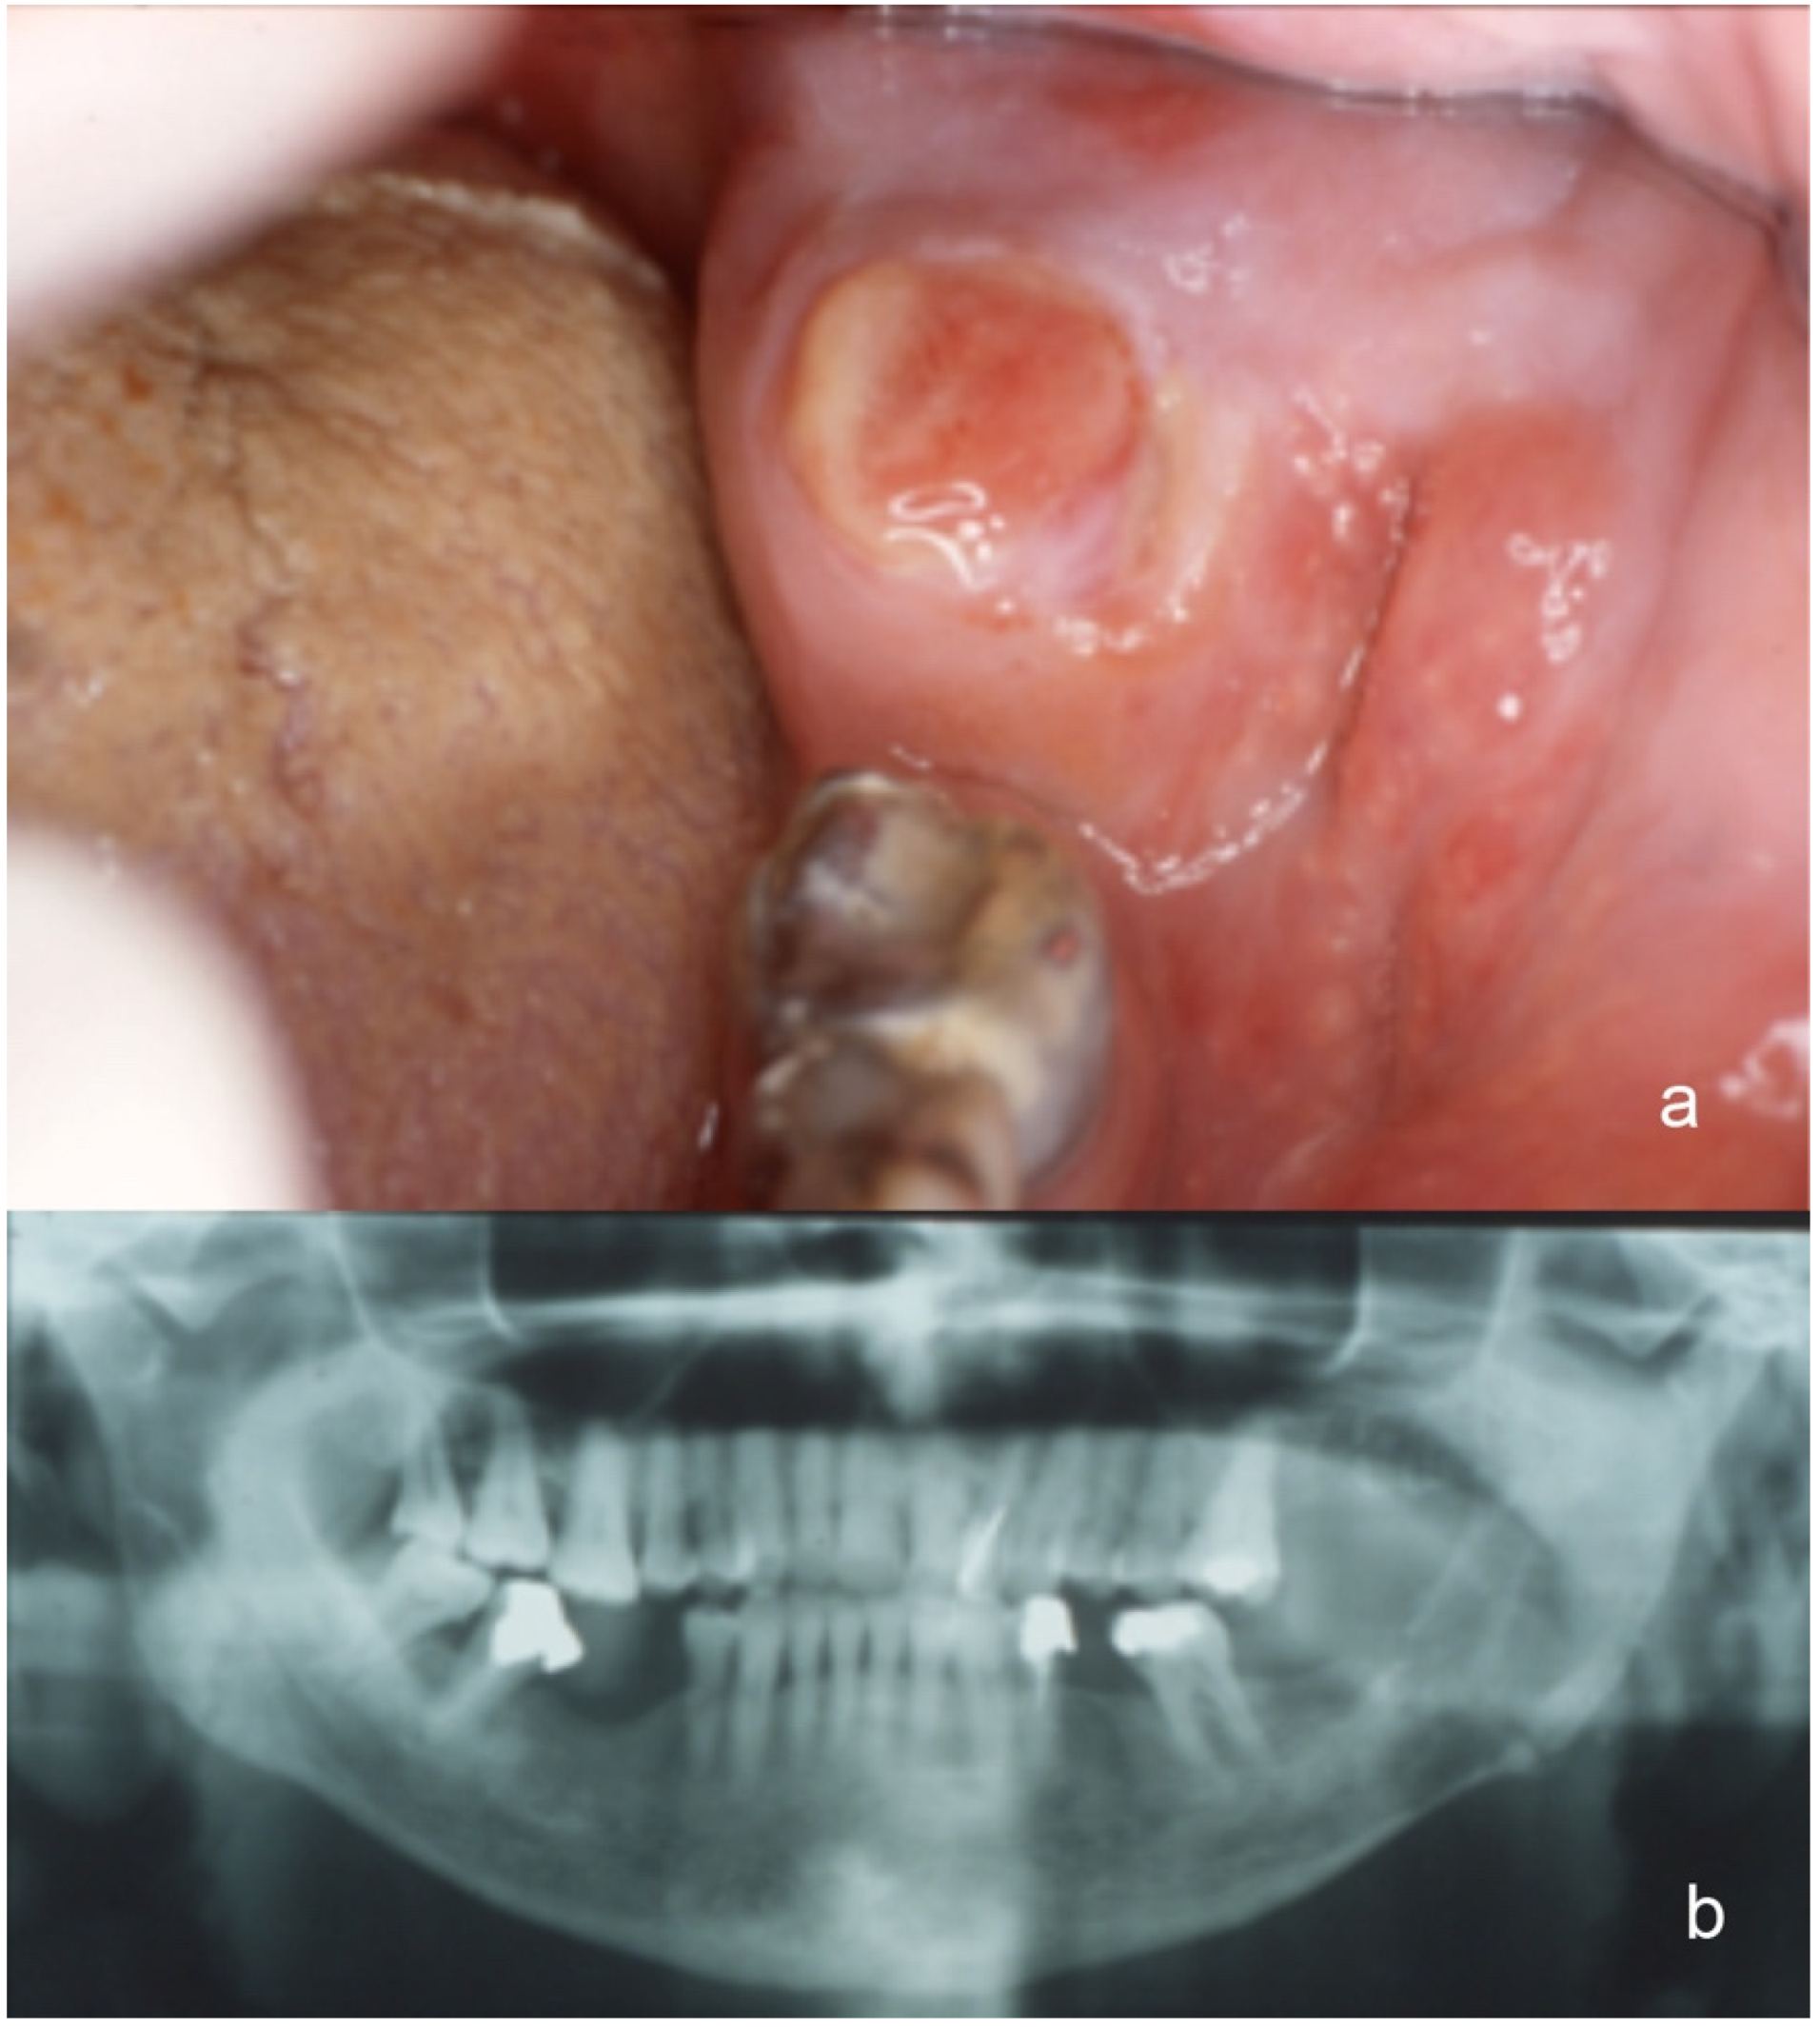

| 1 | F | 69 | Gingiva | 5 cm | No | Lungs |

| 2 | M | 56 | Tongue | 4 cm | No | Thyroid, opposite kidney, finger |

| 3 | M | 45 | Mandible | 5.5 cm | No | - |

| 4 | M | 63 | Mandible | 5 cm | Yes | Vertebra |

| 5 | M | 55 | Parotid Gland | 2.2 | Yes | - |

| 6 | F | 55 | Parotid Gland | 1.8 | No | - |

| 7 | M | 60 | Mandible | 3.5 cm | No | - |